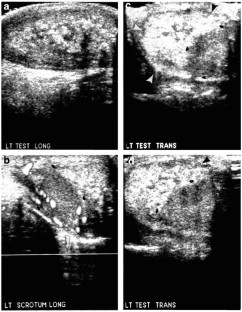

Herman, T., Siegel, M. Meconium Periorchitis. J Perinatol 24, 53–55 (2004). https://doi.org/10.1038/sj.jp.7211014